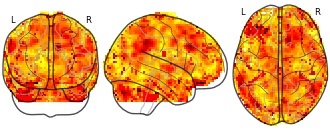

"name": "VBM_HeterogeneityMap",

"description": "Abnormal gray matter in BPD. Brain regions with significant heterogeneity (i.e. between-study variance) in the comparison of patients with BPD and healthy controls. Results are thresholded at at p<.005 & k>20. Note: Results are based on meta-analysis of group comparisons. Note2: Results were updated (see Erratum for this publication)",

"add_date": "2016-01-21T18:23:32.131003+01:00",